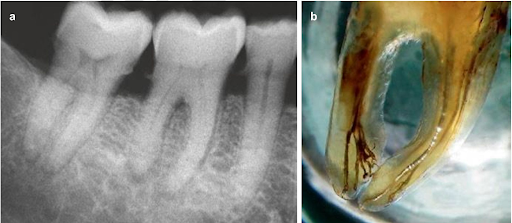

Trong những thập kỷ qua, đã có một số phương pháp nghiên cứu về giải phẫu răng và giải phẫu ống tủy; như mô học, X quang, lọc răng (tooth clearing), chụp cắt lớp vi tính hiển vi (micro – CT). Tooth clearing (lọc răng, làm trong răng) cho

phép quan sát giải phẫu ống tủy theo 3 chiều, và trên thực tế nó cung cấp thông tin chính xác hơn phim cận chóp.

(a) Phim cận chóp răng cối lớn thứ nhất hàm dưới trước khi nhổ. (b) Hình ảnh răng sau khi được làm trong suốt. Giải phẫu phức tạp được quan sát một cách rõ ràng.